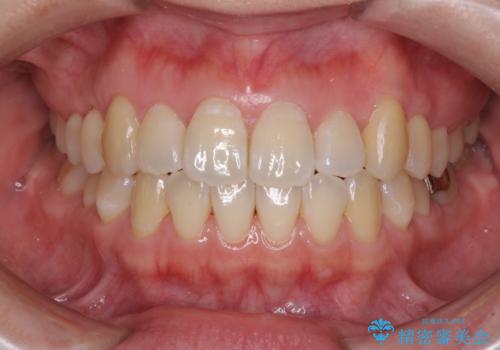

前歯のデコボコを改善 インビザライン矯正

担当医 藤巻太一朗